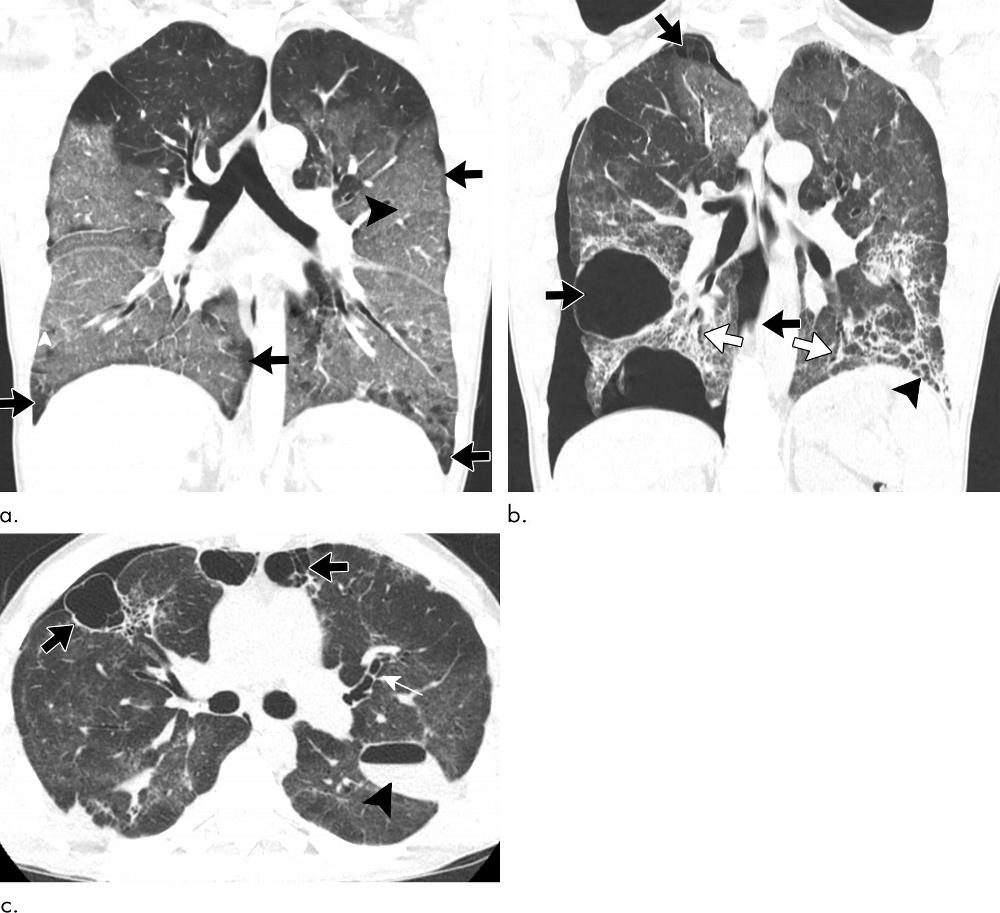

Figure 3. Images show electronic cigarette or vaping product use–associated lung injury with organizing pneumonia pattern secondary to vaping tetrahydrocannabinol in an 18-year-old man. (a) Posteroanterior radiograph shows midlung and lower lung consolidation and opacity bilaterally. Small right pleural effusion (black arrowhead) and septal thickening (white arrowhead) are seen. There is conspicuous sparing of cardiac borders (white arrows) as well as subpleural portions of lung (black arrows). (b) Coronal and (c) sagittal oblique images from CT nicely illustrate radiographic findings with mild and lower lung–predominant ground-glass opacity with few areas of consolidation. Prominent subpleural and perilobular sparing is present (black arrows). In addition, there is conspicuous sparing of peribronchovascular interstitium, best illustrated around larger pulmonary arteries and veins (white arrows). Hazy upper lobe–predominant ground-glass centrilobular nodules are present bilaterally (white arrowheads). In addition to thickening of interlobular septa, there are few areas with thickening of intralobular septa creating “crazy paving” pattern (black arrowheads). (d) Three days after initiation of steroids, patient showed dramatic clinical and radiographic improvement.

High-res (TIF) version